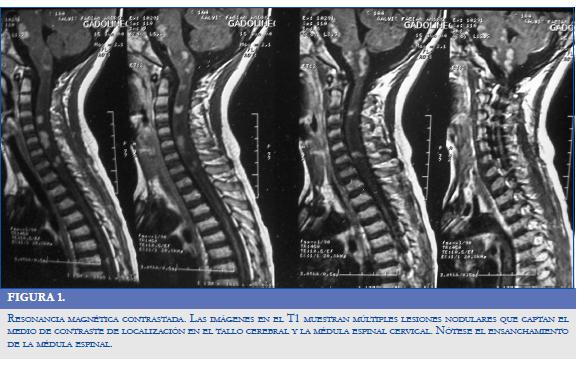

El 10/06/04 reingresó por empeoramiento de sus condiciones generales; se encontró soñoliento, con disminución de la agudeza visual, papiledema bilateral, nistagmo vertical y ataxia troncular. Se le solicitó resonancia magnética (RM) de cerebro y de columna cervical, simple y contrastada (Figura 1); las imágenes diagnósticas realizadas el 15/06/04 evidenciaron múltiples lesiones nodulares hipointensas en el T1 e hiperintensas en el T2 que captaban el medio de contraste paramagnético de localización en el tronco cerebral y la médula espinal cervical; esta última se encontró ensanchada desde C1 hasta C7; además existía hidrocefalia obstructiva por obstrucción acueductal con edema transependimario y cerebral.